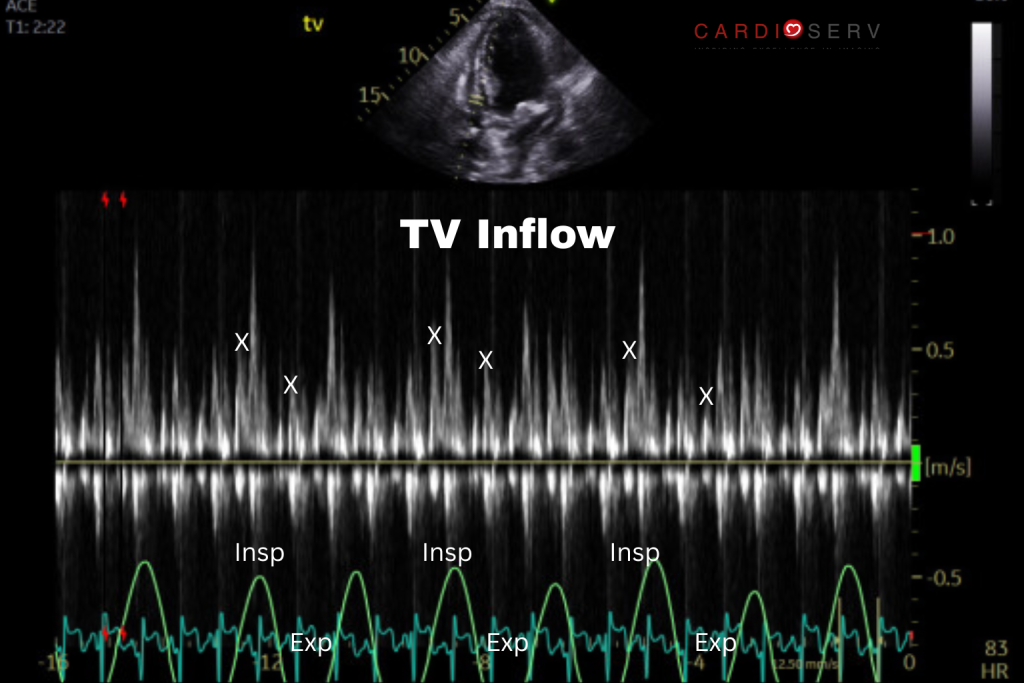

Tricuspid Valve Inflow

>60% increase of peak E wave velocity with inspiration, decrease with expiration.

How to Evaluate Respiratory Variation

Technique:

- View: Apical 4-chamber

- Mode: Pulsed-Wave Doppler

- Cursor position: At leaflet tips, parallel to flow

- Sweep speed: 25-50 mmHg (slow)

- Respiratory cycle: Label inspiration/expiration; record ≥3 full cycles